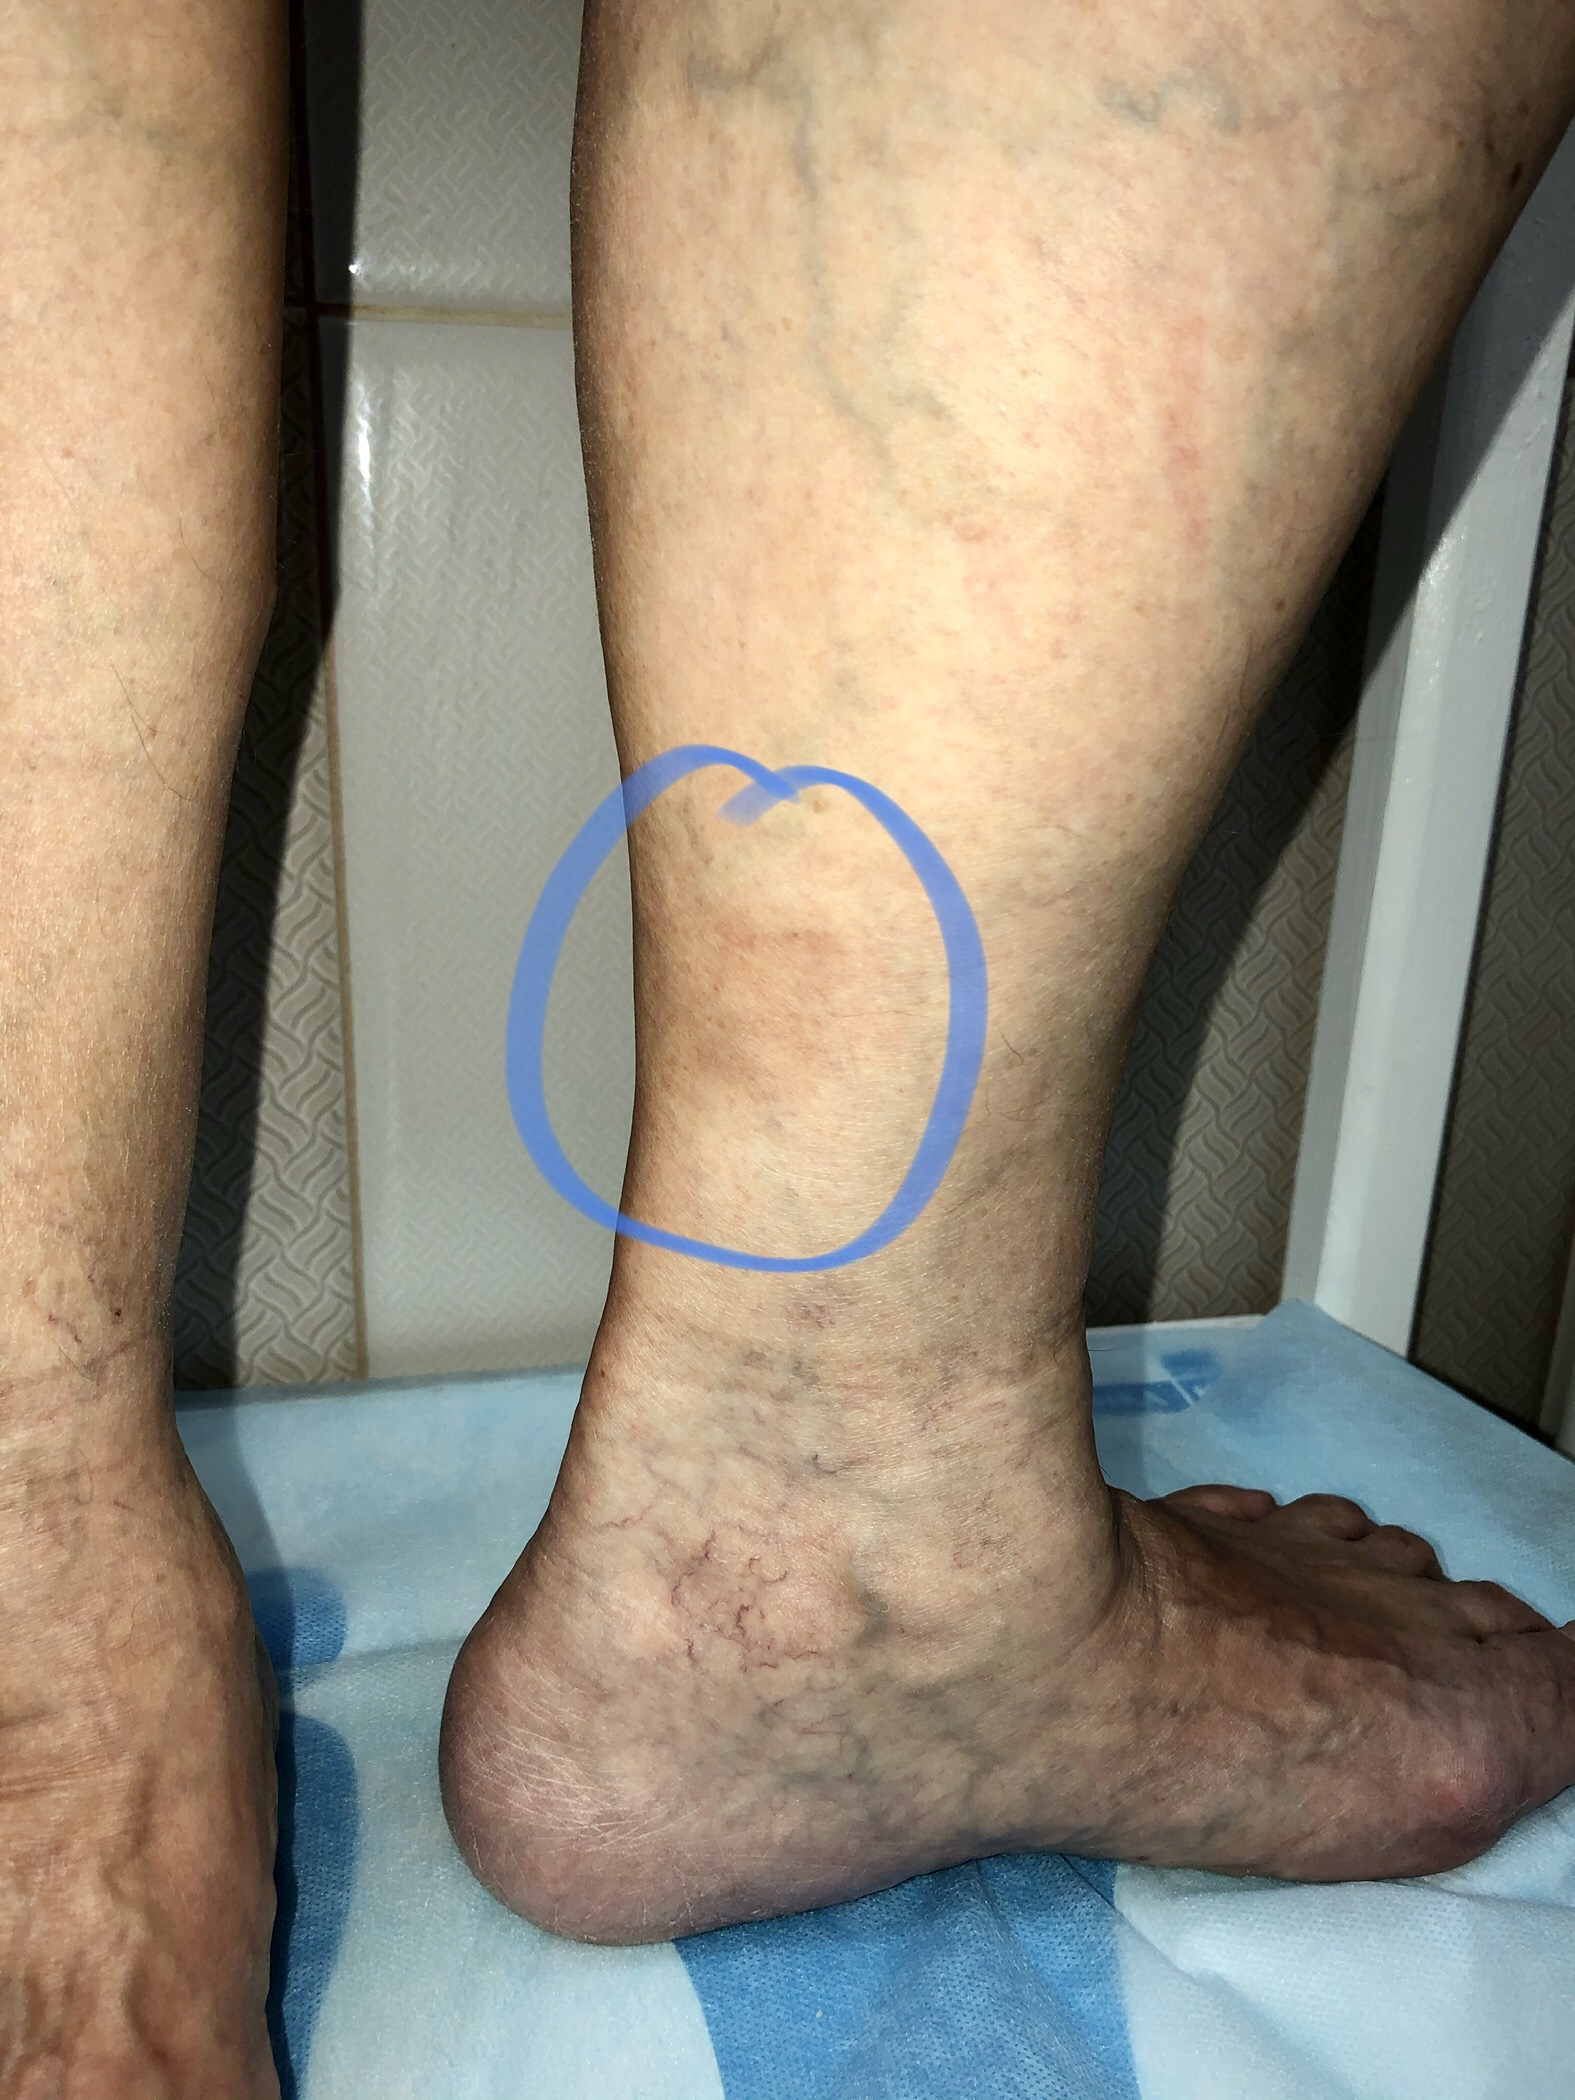

Очень часто флебологу нужно проводить диагностику, когда жалобы пациента связаны с проблемами суставов и связок. Например артрит коленного сустава может проявляться болями с любой стороны колена, а вовсе не только спереди. И отек может быть гораздо выше и ниже самого сустава. В диагностике помогает анамнез и все-таки измененные контуры сустава. Явная его деформация, по сравнению с не больным своим собратом. Нахождение кист в проекции сустава также нередко, и вовсе не всегда пациент нам говорит о болях. Многие существуют незаметно. Разрыв вот такой кисты Бейкера, если говорить правильно приводит к болевому синдрому и иногда значительному отеку в области колена и ниже, почти до лодыжек. Вот тогда опять же без УЗИ можно легко ошибиться в диагнозе и начать неправильное лечение.

Болезни связочного аппарата

Болезни связочного аппарата и суставов в области голеностопного сустава и на стопе вообще очень распространены. Отдельный ручеек идет к флебологу, если есть видимые вены или значительный отек. Всегда помогает в случае болевого синдрома знание, где что может болеть и конечно локальность самой боли наводит на мысли о патологии связок и суставов. И сколько таких пациентов флеболог отправляет к ортопеду! Фото от доктора Андрея Коновалова.